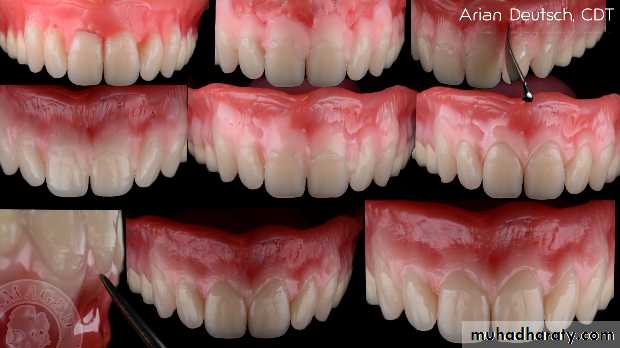

LIP EXAMINATION:

Lip support

Lip length

Lip thickness

Lip mobility

Health of the lips

LIP SUPPORT – adequately supported

- unsupported

Contour and appearance of the

vermillion border usually are altered

by tooth loss

Placement of anterior teeth

If the anterior teeth are set too far lingually or palatally, lips will lack the necessary support.

Unsupported lip

How much tooth will be exposed ?

Determinant in anterior teeth selection.

Lip length is classified as -

A. Long B. Medium C. Short

lip line , smile line classification:

A high lip line

Low lip line

Normal lip line

Lip thickness:

Thick lips – need lesser support from the artificial teeth and the labial flange.

Thin lips – rely on the appropriate labiolingual position of the teeth, for their fullness and support